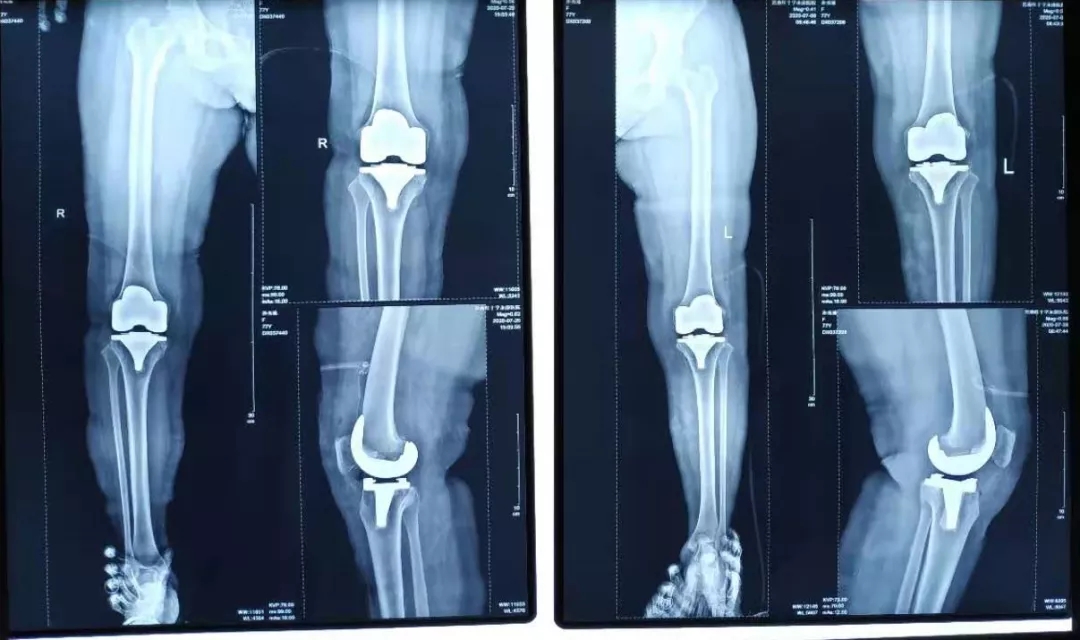

术中处理:双侧间隔一周,均采用股四头肌snip切口入路,术程顺利。术中患膝屈伸活动可达到0°~100°,术后24小时开始屈伸功能锻炼,术后5天屈伸活动达到0°~100°。

术后影像:

于是更改康复计划,强化被动伸膝同时,加强股四头肌力量训练,不再加强被动屈膝训练。术后3个月随访时,患者主被动屈伸膝范围达到0°~100°,左侧伸膝迟滞基本消失,行走时已无度“打软腿”现象。HSS评分左膝85分,右膝88分。